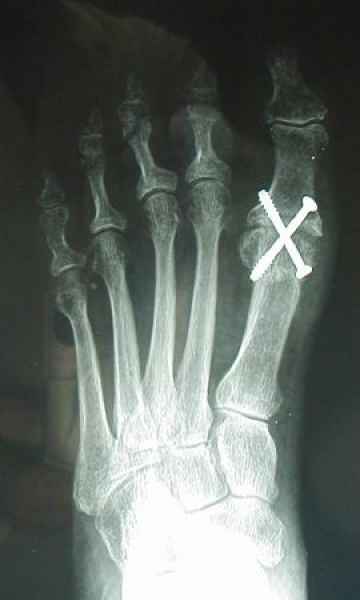

La marcha no solo es característica de la especie humana sino también de cada persona, y más aún varía según el estado de ánimo del momento. Una patología en los pies, se traduce en el rostro, en el ánimo, en el psiquismo. No sólo el dolor produce estos efectos, también un pie deformado o poco estético. En nuestra sociedad, la estética constituye un valor muy apreciado y estas alteraciones causan vergüenza fundamentalmente en las mujeres, que esconden en la playa sus pies en la arena y no pueden usar calzados elegantes.